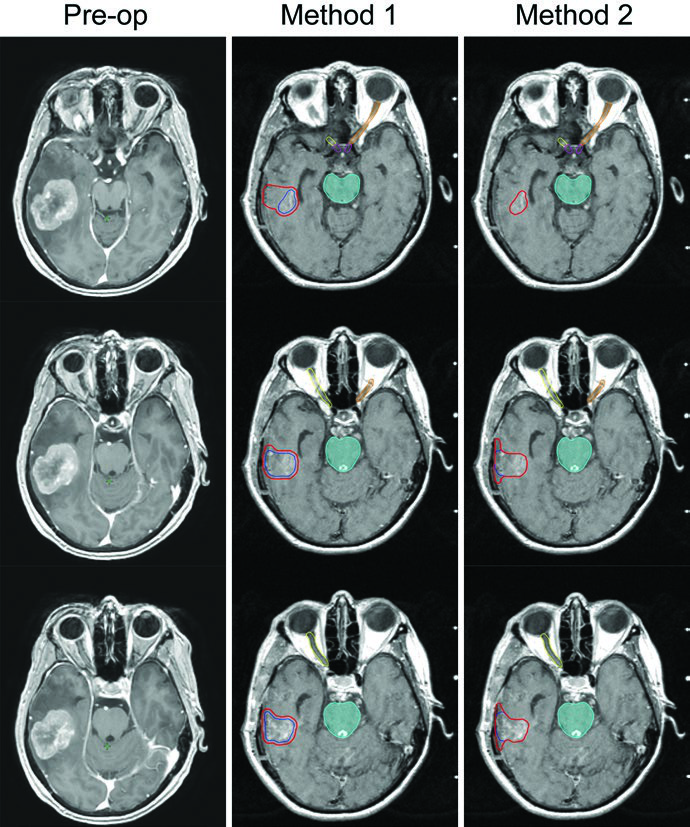

O delineamento varia significativamente entre metástases intactas e cavidades pós-cirúrgicas. Para lesões intactas, o processo é direto: o GTV é a lesão captante de contraste na sequência T1 da RM, e o CTV é GTV + 0 mm — sem margem adicional. Já para cavidades pós-ressecção, existem dois métodos bem estabelecidos na literatura, cada um com filosofia distinta de margem.

| Cavidade pós-ressecção (Método 1 — Soltys et al.) | n/a | Margem de expansão de 2 mm uniforme ao redor das bordas da cavidade de ressecção visualizadas na RM pós-contraste |

| Cavidade pós-ressecção (Método 2 — Soliman et al.) | n/a | Toda região captante + cavidade + trajeto cirúrgico na RM pós-operatória; 5–10 mm ao longo do retalho ósseo se contato dural prévio; 1–5 mm se sem contato dural; 1–5 mm ao longo do seio venoso se contato prévio |

O Método 2 de Soliman et al. é mais conservador e tende a gerar volumes de CTV maiores. No exemplo da figura, uma cavidade de 24 mm no lobo temporal esquerdo — após ressecção total de metástase de 33 mm de câncer retal primário com contato dural pré-operatório mas sem contato com seio venoso — receberia margem de 10 mm ao longo do retalho ósseo. A fração única foi escolhida pelo tamanho pequeno da cavidade (<3 cm) e distância suficiente de estruturas cerebrais delicadas. No Gamma Knife, PTV = CTV sem expansão adicional. O Método 1 (Soltys) aplica simplesmente 2 mm uniformes ao redor da cavidade visualizada na RM T1 pós-gadolínio, resultando em volume menor e potencialmente menos toxicidade.